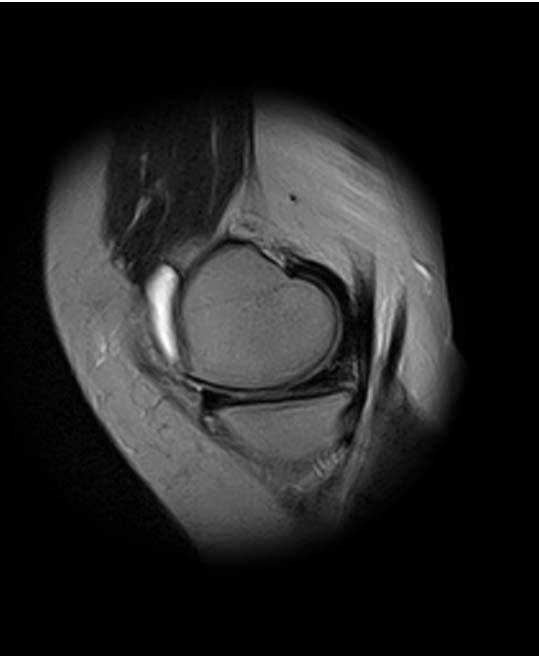

1. травма 5 лет назад - "ударилась коленом", с тех пор боли в суставе

3. стандартные рентгенограммы с небольшими изменениями - сужение

медиальной суставной щели

4. вес пациентки 80 кг, рост 165

5. сустав клинически стабилен